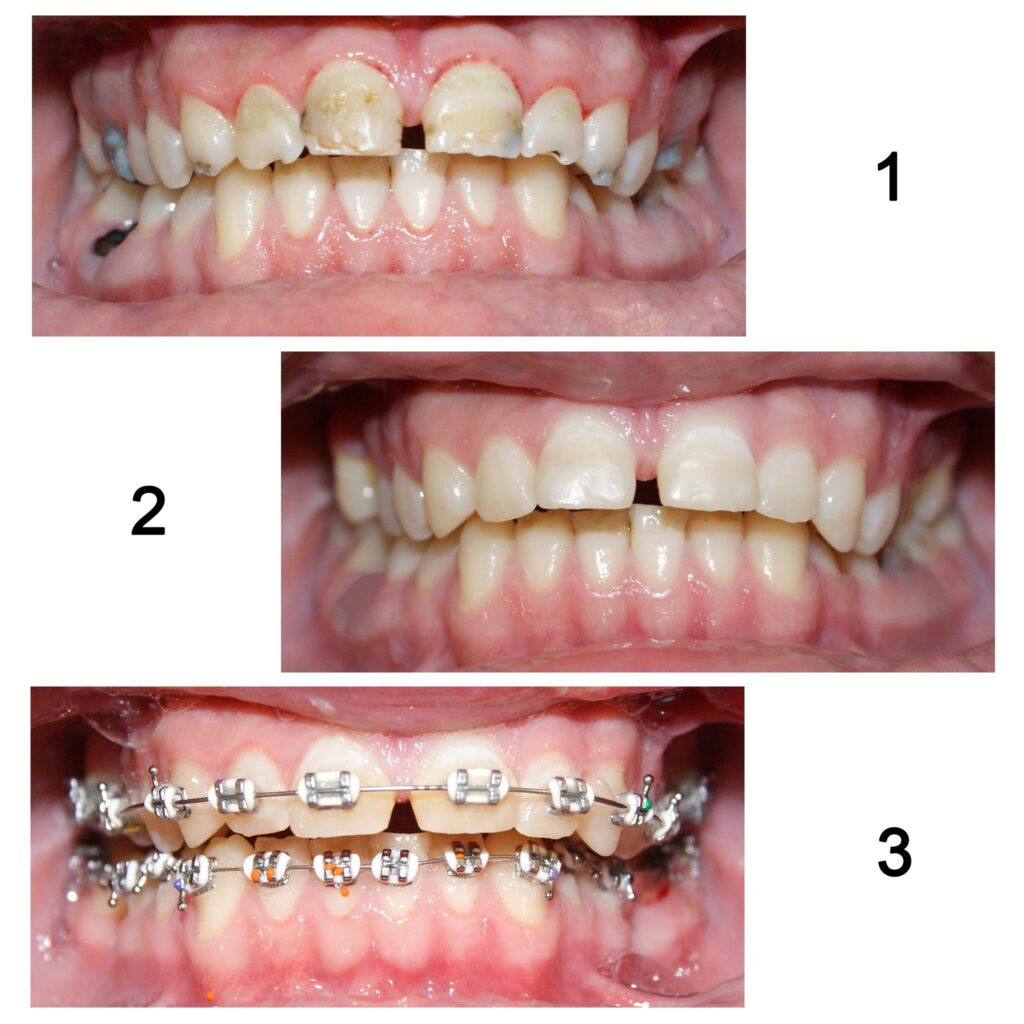

Aparatele ortodontice se aplică doar pe dinții curățați în prealabil. Cariile și resturile radiculare irecuperabile trebuie asanate după cum se vede aici